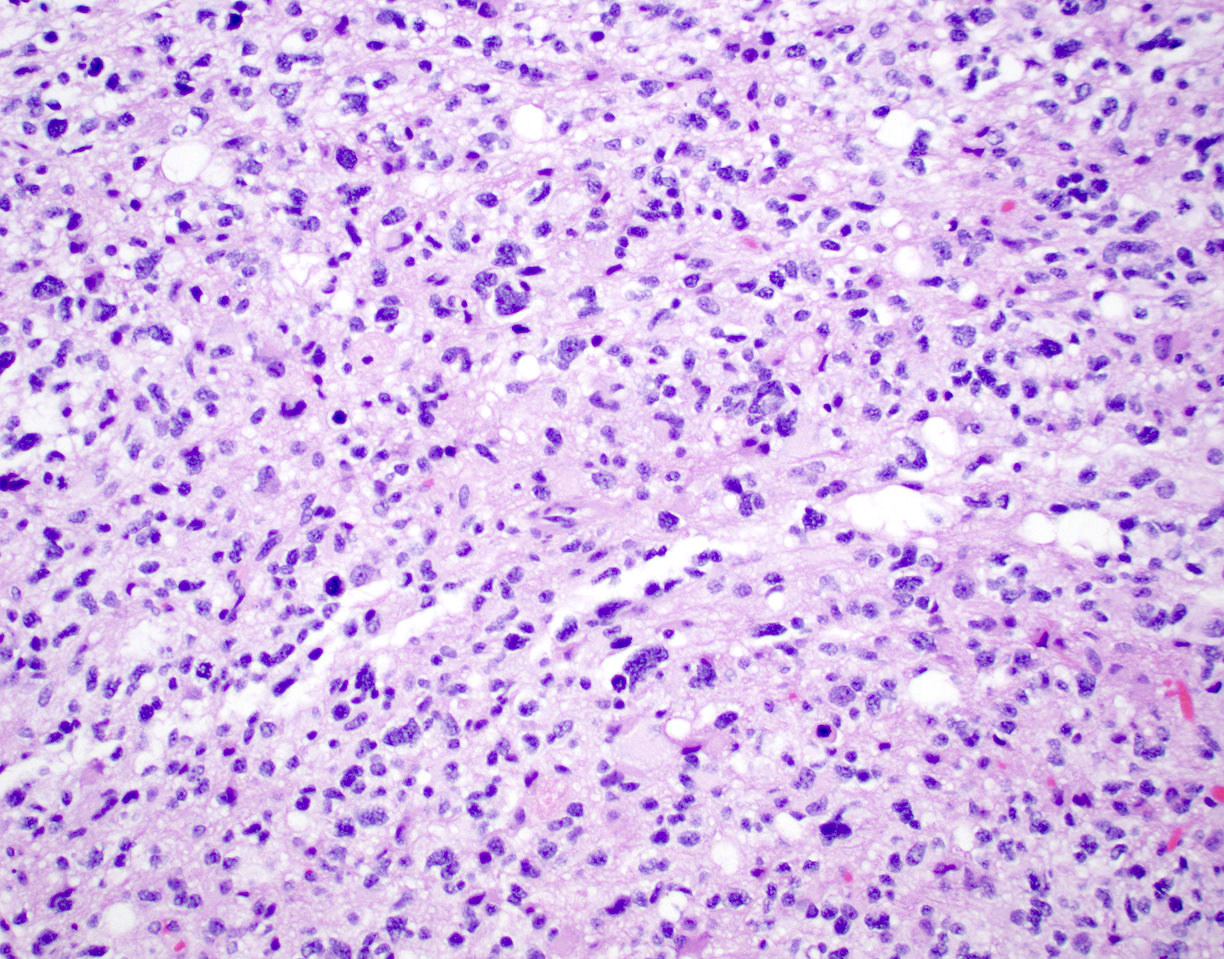

Microscopic (histologic) description

- Diffusely infiltrating tumor cells with oval to elongated astrocytic nuclei and varying appearance of tumor cytoplasm and fibrillar glial processes (Acta Neuropathol 2015;129:789)

- At the periphery, tumor cells may infiltrate in a diffuse single cell pattern, often with entrapped neurons and axons

- Cellular morphology is variable, even within a single tumor

- Commonly there is a mix of cells with elongated nuclei and fine fibrillar processes, cells with eccentric nuclei and glassy eosinophilic cytoplasm (gemistocytes), larger pleomorphic cells and small cells with scant cytoplasm

- May show oligodendroglioma-like areas

- Myxoid background and microcyst formation may be present

- Variable mitotic activity, cellularity and nuclear atypia depending on CNS WHO grade

- In small biopsy specimens, the presence of 1 mitosis may be sufficient for a CNS WHO grade 3 diagnosis, while the presence of a few mitotic figures in a large resection would not be sufficient for grade 3 designation (Acta Neuropathol 2020;139:603)

- Presence of necrosis or microvascular proliferation would be consistent with a CNS WHO grade 4 designation

Microscopic (histologic) images

Contributed by Eman Abdelzaher, M.D., Ph.D., John DeWitt, M.D., Ph.D. and Meaghan Morris, M.D., Ph.D.

B. If R132H IDH1 immunohistochemistry is positive, ATRX staining of tumor cells is expected to be lost. The image is consistent with an infiltrating astrocytoma with significant pleomorphism and mitotic activity. If R132H IDH1 immunohistochemistry is positive, as stated in answer B, the findings are then consistent with astrocytoma, IDH mutant, CNS WHO grade 3. Astrocytoma, IDH mutant tumors often show concurrent ATRX mutation, indicated by loss of staining in tumor cells with ATRX immunohistochemistry.

C. Mitoses and pleomorphism in the absence of necrosis, microvascular proliferation or CDKN2A / CDKN2B homozygous deletion. The presence of mitoses and pleomorphism in the absence of necrosis, microvascular proliferation or CDKN2A / CDKN2B homozygous deletion is consistent with a diagnosis of astrocytoma, IDH mutant, CNS WHO grade 3. The presence of necrosis, microvascular proliferation or CDKN2A / CDKN2B homozygous deletion would be consistent with astrocytoma, IDH mutant, CNS WHO grade 4. An infiltrating astrocytoma with IDH mutation and no significant proliferative activity, pleomorphism, necrosis, microvascular proliferation or CDKN2A / CDKN2B homozygous deletion would be consistent with astrocytoma, IDH mutant, CNS WHO grade 2.